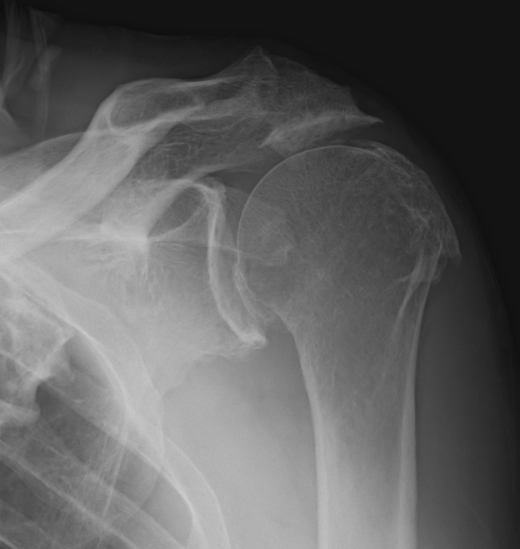

Chronic massive rotator cuff defect associated with high riding humeral head

- acetabularisation of the acromion

- glenohumeral osteoarthritis

Xray

Superior migration of head without arthropathy

Acetabularization of the acromion and osteoarthritis